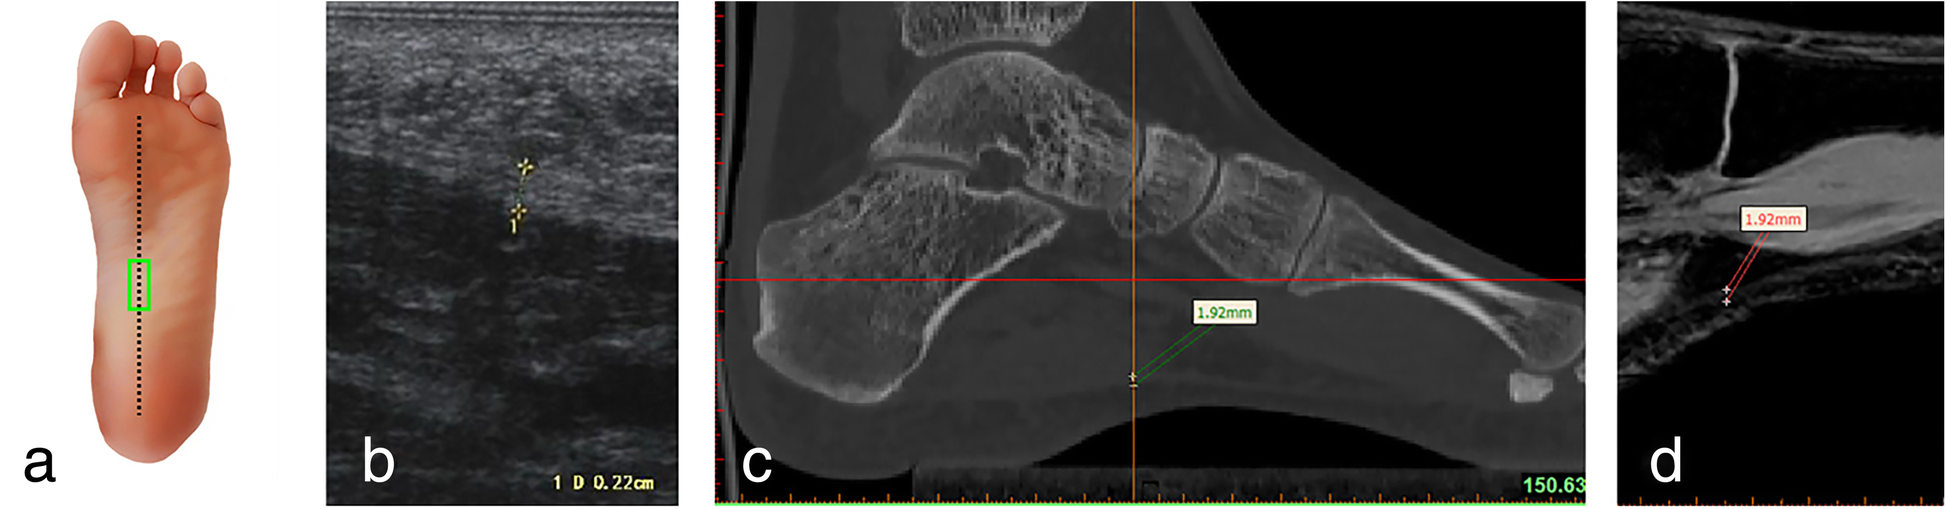

Fig. 3

Ultrasound, CT and MRI measurements of the arch of the plantar fascia (longitudinal section) a Ultrasonic probe is placed (green panel). b Ultrasonic measurement. c Measuring the thickness of the plantar fascia reconstruction CT images. d Measuring the thickness of the plantar fascia reconstruction MRI images